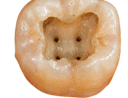

Shapes of the access cavity of all teeth

| Tooth | Access cavity shape | Average depth |

|---|---|---|

| Maxillary incisors | Triangular or oval (placed over the palatal surface) |

3-4 mm |

| Maxillary molars | Trapezoidal (located over the mesial buccal cusp or the central part of the tooth)

|

5-6 mm |

| Mandibular molars | Trapezoidal or rhomboidal (centered over the mesial buccal cusp)

|

5-6 mm |